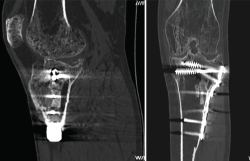

4. Prótesis (Figura 27)

Figura 27. Corte de reconstrucción sagital y coronal de tomografía axial computarizada de rodilla: se valoran los componentes femoral y tibial de la prótesis total.